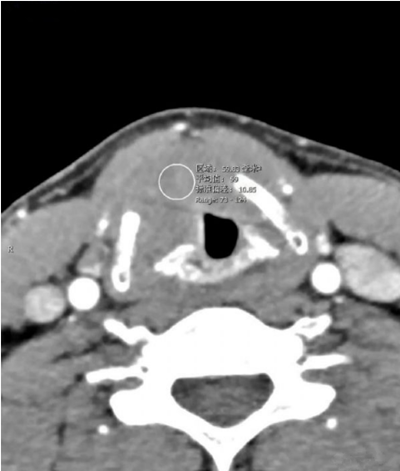

声门层面右侧声带增厚,呈结节状软组织密度影,边界尚可见,前联合及左侧声带前1/2受累,声门左偏,周围脂肪间隙小时,右侧甲状软骨骨质破坏。增强扫描呈轻度延迟强化。